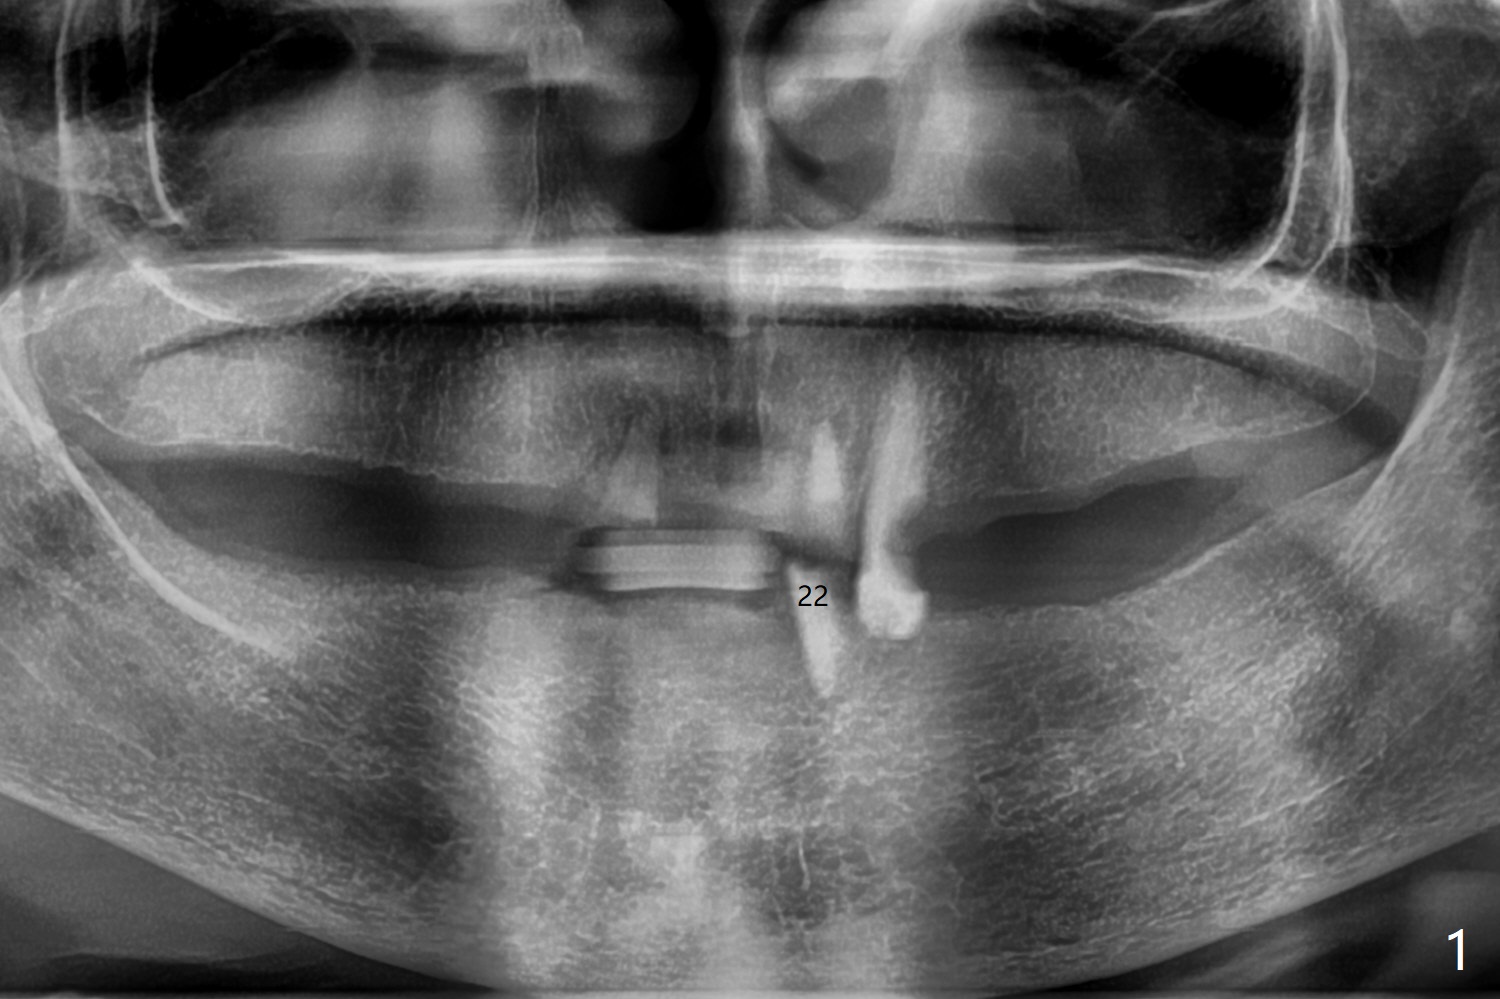

A 79-year-old woman wants to extract the remaining teeth gradually because of occasional tenderness in the root tip (Fig.1). After discussion, she barely agrees to have bone graft after #22 extraction. The buccal plate is low, while there is large apical perforation. Cortical allograft is covered with 8x8 mm BioXclude and sutured with 4-0 PGA. It appears that bone graft is necessary for most extraction. 术后8天胎盘膜(图二:B)似乎帮助牙槽窝口愈合,固定骨粉(图三:*)。